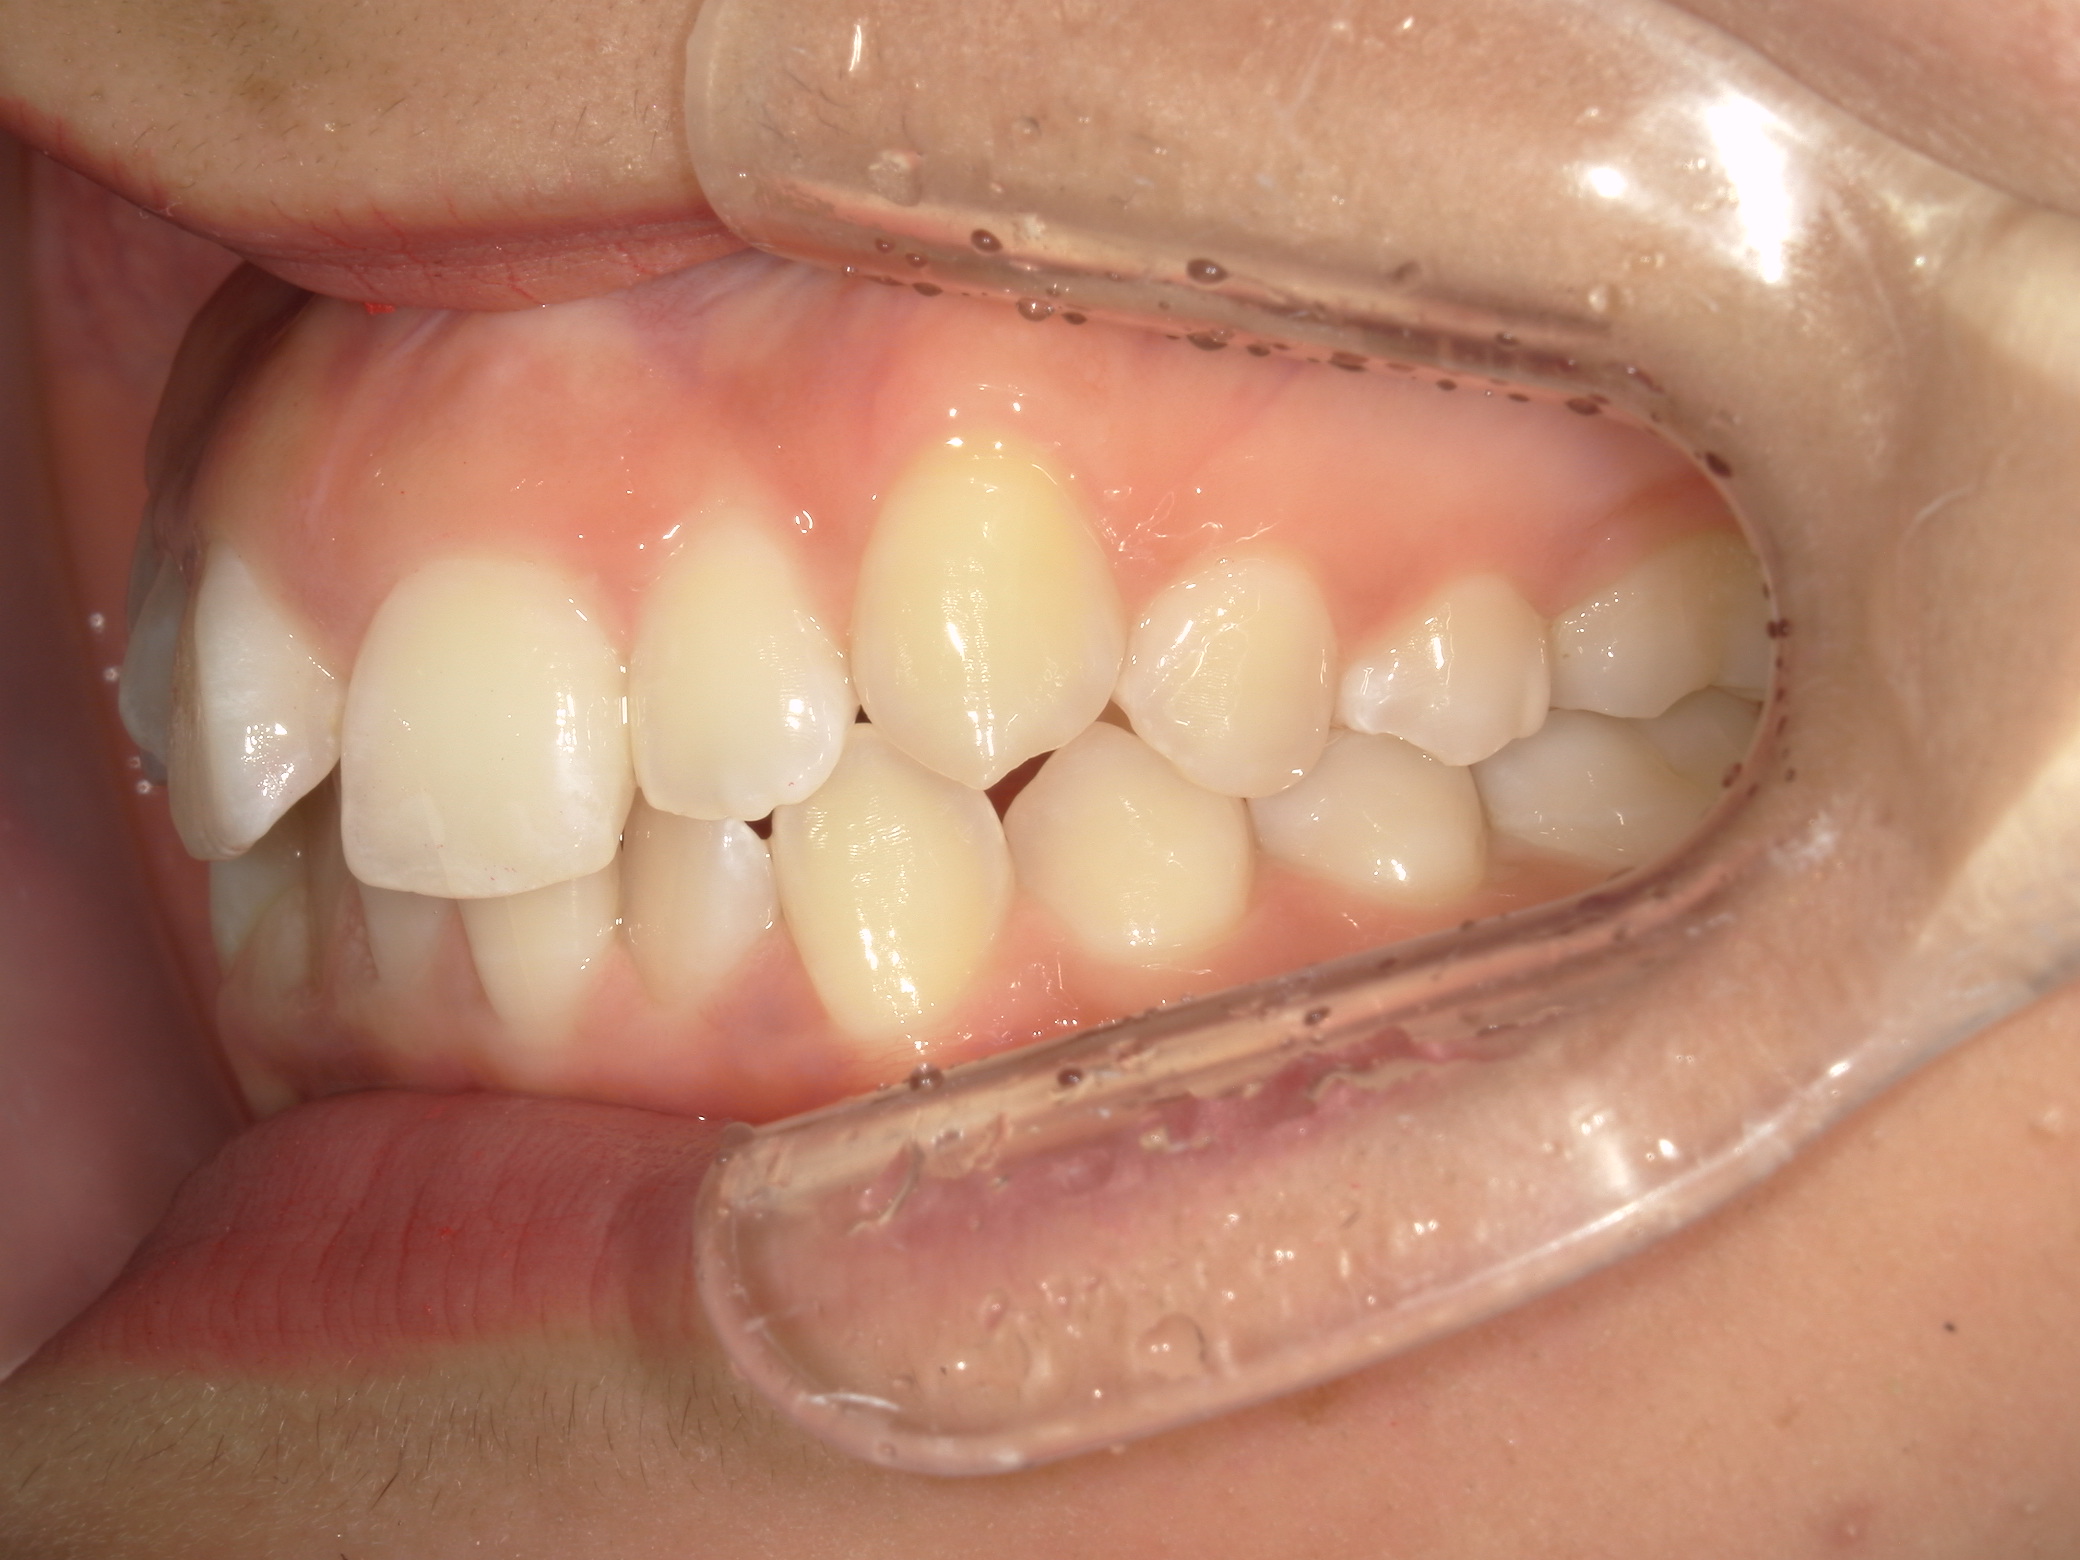

プチワイヤー矯正 症例(54)

ミニインプラント(2本)、スライスカットを併用。

治療の流れ

カテゴリー : ガタガタ(叢生)